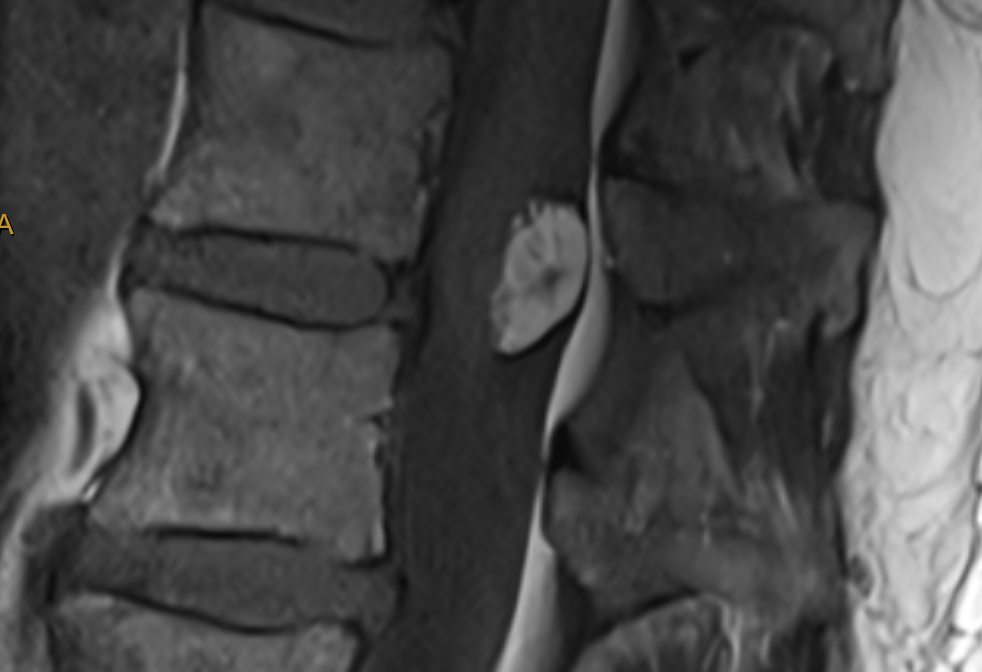

A sagittal MRI scan of the lower spine showing the spinal cord extending lower than normal, attached to a mass.